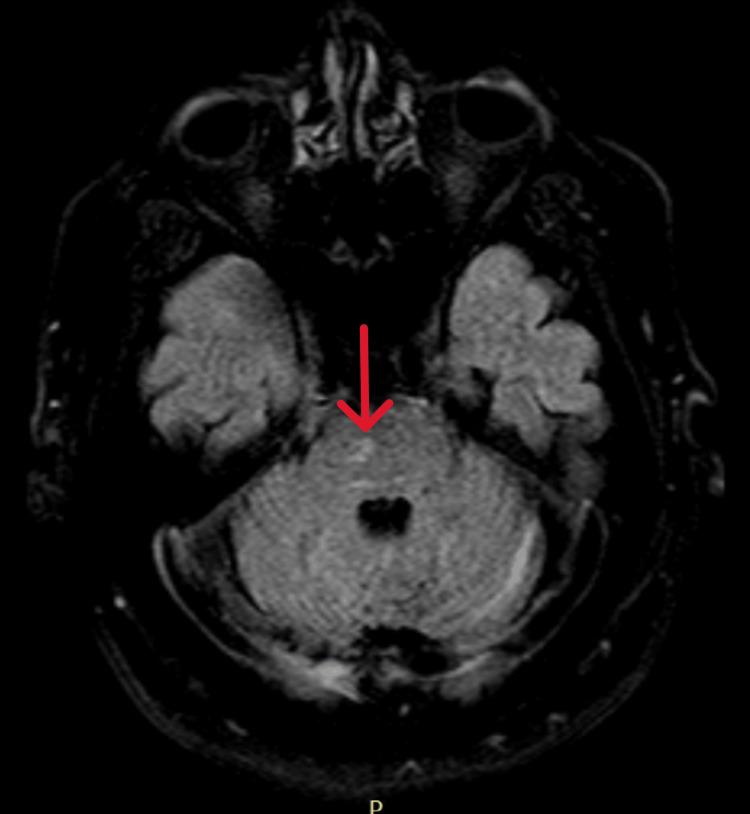

Hashimoto's encephalopathy (HE) is a rare autoimmune disorder, typically associated with Hashimoto's thyroiditis, and often presents with rapidly progressive cognitive impairment, psychiatric symptoms, and neurological deficits. Since the first case reported, there have been relatively few reports of HE cases, and it remains rare in Central America. A 59-year-old male patient with a past medical history of hypertension (HTN) and type 2 diabetes mellitus (DM2) was hospitalized due to a one-month history of rapidly progressive cognitive impairment associated with behavioral changes and episodes of amnesia. It was not associated with motor or sensory deficits, seizures, or movement disorders. Given this presentation, alongside normal head CT findings and mild age-related brain atrophy on MRI, the initial diagnosis posed a challenge. Further investigations, including cerebrospinal fluid (CSF) analysis, autoimmune panels, and viral encephalitis testing, helped exclude other potential causes of encephalopathy. Notably, elevated anti-thyroid peroxidase (anti-TPO) and anti-thyroglobulin (anti-TG) antibodies were detected, strongly suggesting HE. The patient responded favorably to immunosuppressive treatment with intravenous methylprednisolone and subsequent oral prednisone, leading to significant cognitive improvement and recovery of function. This case highlights the importance of considering HE in the differential diagnosis of rapidly progressive cognitive decline, especially when routine standard investigations do not reveal an alternative cause.

桥本脑病(HE)是一种罕见的自身免疫性疾病,通常与桥本甲状腺炎相关,常表现为快速进展的认知障碍、精神症状和神经功能缺损。自首例病例报告以来,HE病例的报道相对较少,在中美洲地区仍然罕见。一名59岁男性患者,有高血压(HTN)和2型糖尿病(DM2)病史,因1个月来快速进展的认知障碍伴行为改变和失忆发作而住院。该症状与运动或感觉功能缺损、癫痫发作或运动障碍无关。鉴于此临床表现,以及头颅CT检查结果正常和MRI显示轻度与年龄相关的脑萎缩,初步诊断颇具挑战性。进一步检查,包括脑脊液(CSF)分析、自身免疫指标检测和病毒性脑炎检测,有助于排除其他潜在的脑病病因。值得注意的是,检测到抗甲状腺过氧化物酶(抗-TPO)和抗甲状腺球蛋白(抗-TG)抗体升高,强烈提示为HE。该患者对静脉注射甲泼尼龙及随后口服泼尼松的免疫抑制治疗反应良好,认知功能显著改善,功能得以恢复。本病例强调了在快速进展性认知衰退的鉴别诊断中考虑HE的重要性,尤其是在常规标准检查未发现其他病因时。